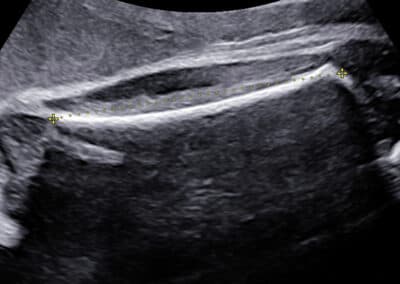

Ultrazvukové vyšetření provádíme přes břišní stěnu. Močový měchýř maminky nemusí být naplněný, miminko je totiž již vysoko v břišní dutině.. Určíme uložení a stav placenty, množství plodové vody a počet cév v pupečníku. Změříme velikost příčného průměru a obvodu hlavičky, obvod bříška, délku stehenní kosti a vyšetříme podrobně všechny orgány miminka. Pokud nebudete znát pohlaví miminka a budete si ho přát vědět, rádi vám jej sdělíme. Budete-li si přát připojit 3D-4D ultrazvukové vyšetření s reálným zobrazením vzhledu miminka , rádi jej připojíme. Při vyšetření se řídíme zásadami Fetal Medicine Foundation a všichni lékaři mají FMF certifikát na všechna ultrazvukové vyšetření ve druhém trimestru.

Vyšetření obvodu hlavičky

Vyšetření délky stehenní kosti